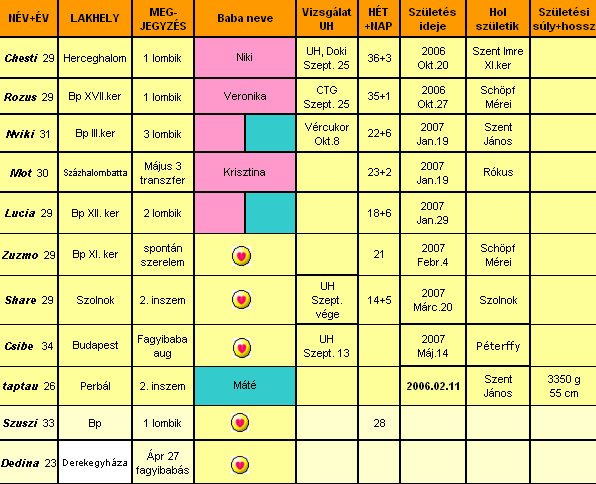

Néhány napig nem voltam gép-közelben. Látom, beindultak a talis szervezések.

Chesti, húúúú, 25 nap! Eszméletlen! Megértem, hogy nem mert elutazni a férjed.

Táblázatba légyszíves írd meg, hogy UH október 3-án lesz. Aznap töltjük a 16. hetet, és a dokim meg akarja még az AFP előtt nézni, hogy tényleg akkora-e. Még 1 hét, és újra láthatjuk.